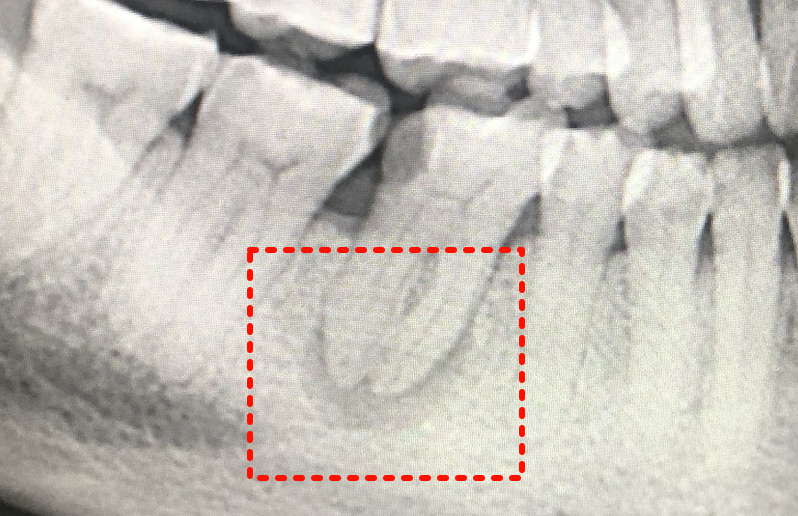

- X线检查:

- 根尖周透射影(低密度阴影),边界模糊或清晰(肉芽肿或囊肿可能)。